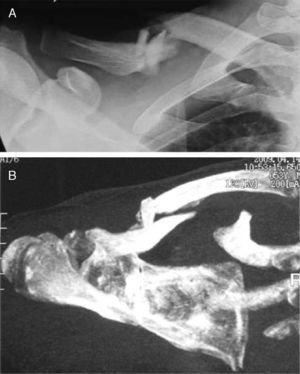

En este estudio pretendemos valorar el resultado obtenido tras el tratamiento de las fracturas conminutas desplazadas (fig. 1) o con un tercer fragmento del tercio medio de la clavícula, mediante la osteosíntesis con una placa anatómica de bajo perfil colocada en la cara superior del hueso.

Material y métodoEntre enero de 2006 y junio de 2010 hemos realizado un estudio retrospectivo que incluye 34 pacientes tratados quirúrgicamente y que presentaban una fractura desplazada del tercio medio de la clavícula (fig. 2). Los criterios de exclusión fueron las fracturas abiertas, edad inferior a 18 años y superior a 60, fractura del tercio proximal o distal, lesiones asociadas de nervios, fracturas asociadas en el mismo lado o en el contralateral, fracturas previas de clavícula, función anormal en el lado lesionado o enfermedad inflamatoria o reumática. Veintinueve de los casos eran varones y 5 mujeres, con una edad media de 43 años (19-57 años). El mecanismo de la lesión fue un accidente de tráfico en 22 casos, traumatismos deportivos en 7 y caídas en 5. Por lo que respecta a la lateralidad, 8 afectaron la clavícula izquierda y 26 la derecha. Para la clasificación de las fracturas de clavícula se utilizó la propuesta por Robinson2. Así, 12 casos correspondieron a fracturas del tipo 2B, 17 fueron del tipo 2B1, y 5 del tipo 2B2.